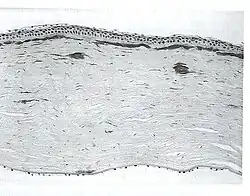

| A network of thick linear corneal opacities in patient with a variant of LCD1 (LCD type III) due to a homozygous p. Leu527Arg mutation in the TGFBI gene | |

Filamentous opacities appear in the cornea with intertwining delicate branching processes. During an eye examination, the doctor sees these deposits in the stroma as clear, comma-shaped overlapping dots and branching filaments, creating a lattice effect. Over time, the lattice lines will grow opaque and involve more of the stroma. They will also gradually converge, giving the cornea a cloudiness that may also reduce vision. The disease is bilateral, usually noted before the end of the first decade of life. Although lattice dystrophy can occur at any time in life, the condition usually arises in children between the ages of two and seven.

In the examination of biomicroscopy, it appears as branches spread on the corneal stroma in the appearance of ghost vessels. diagnosis can also be confirmed with anterior segment OCT (Visante OCT, spectral domain OCT).The interwoven linear opaque filaments have some resemblance to NERVES, but may not be observed in all affected members of families with the condition. Recurrent corneal erosions may precede the corneal opacities and even appear in individuals lacking recognizable stromal disease. Amyloid deposits are found throughout the corneal stroma. Linear and other shaped opaque areas accumulate particularly within the central corneal stroma, while the peripheral cornea remains relatively transparent.